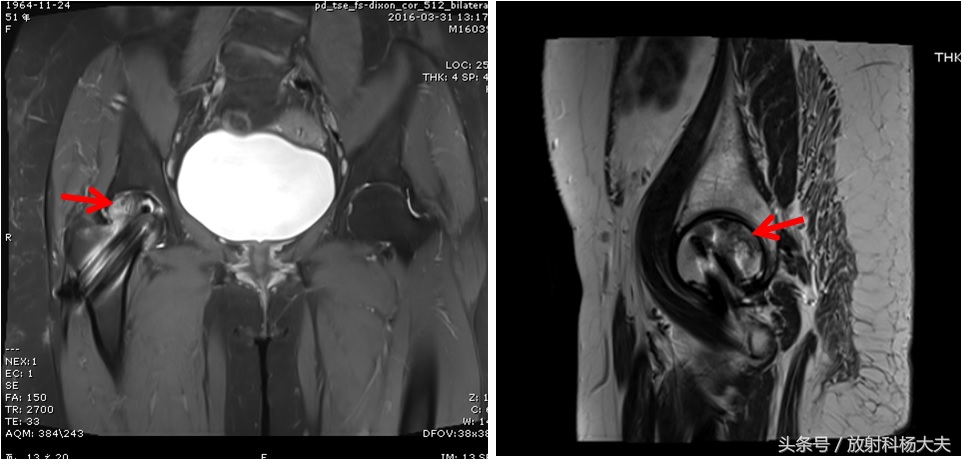

这次复查,来到我院。直接做了MRI。

右侧股骨头缺血坏死!

红箭所示为股骨头缺血坏死的表现,很典型

我们没法去评判上次X光片是否有股骨头坏死,一是因为没有看到片子,二是因为这种早期的股骨头坏死X光平片本身就远远不如MRI敏感(本头条号之前写过此类文章,感兴趣的话可查看下)。